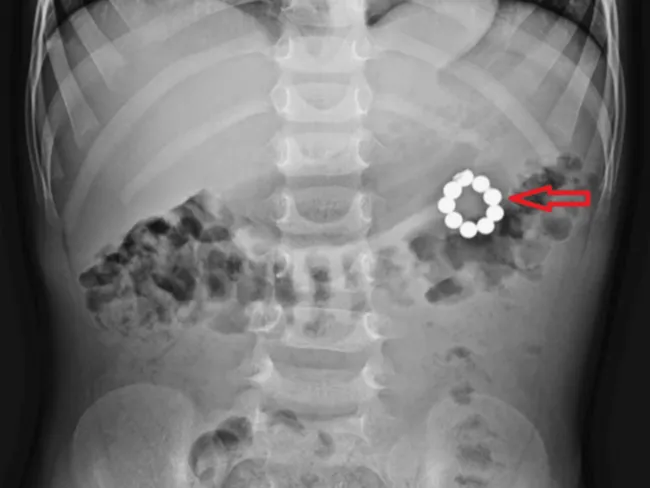

아스가르 알리 병원 의료진은 복부 엑스레이로 이물질을 확인한 후 내시경으로 위의 구슬 5개를 제거했으나, 나머지 4개는 응급 개복술로 꺼냈다. 수술 결과 위와 대장을 잇는 비정상 통로인 위결장 누공이 형성돼 있었으며, 자석의 장기간 압박으로 인한 만성 압박 괴사가 진행된 상태였다.

'복통 3일째' 다섯 살 아이 개복해보니…위에서 대장까지 뚫은 자석 구슬 발견